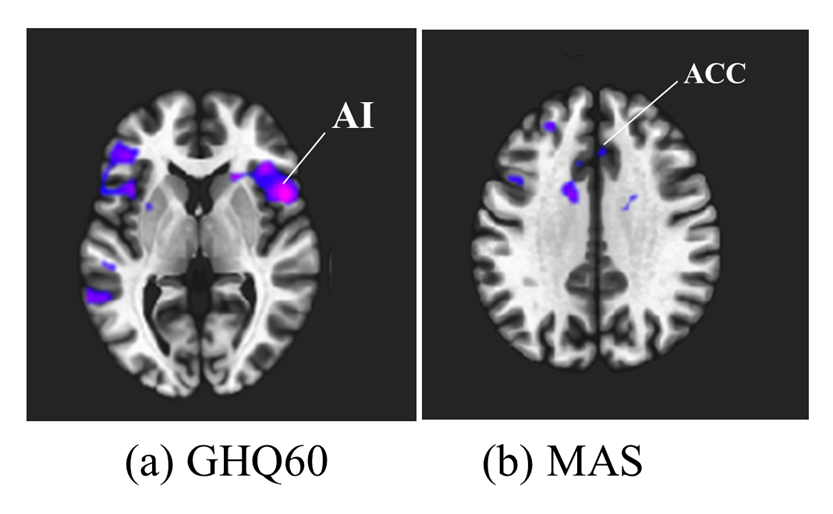

不安に関する脳活動について、これまでは主に精神疾患と診断された方を対象に研究が進められてきました。一方で健常者を対象とした研究は少なく、健常範囲の不安と脳活動の関係は十分には分かっていません。そこで本研究では脳の機能的結合を調べる安静時機能的MRIを用いて健常範囲で強い不安を抱える人の脳活動の変化をネットワークレベルで評価しました。健常範囲でも不安が強い人は認知制御を担う顕著性ネットワーク内の結合が低下することが分かりました。本研究により脳の機能的結合を調べることが精神疾患の早期発見や早期介入に繋がると示唆されました。